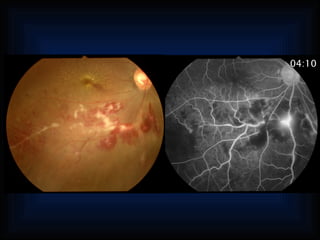

Occlusion of thecentral artery or one of its branches Retinal vessels Occlusion of the carotid Venous: branch occlusion, central vein occlusion Diabetes Vascular occlusion Postirradiation Sickle-cell disease Capillary bed Occlusion of the cartoid Other vaso-occlusive diseases ypofluorescence, After photocoagulation scular filling fect Eales’ disease Ischemic optic neuropathy Vessels of Optic atrophy with decreased capilary b the Optic pit optic nerve Coloboma of the optic nerve Physiology irregular filling of the choroi Occlusion of a choroidal vessel Primay disturbance of choroidal vascular Behcet disease Chorid So-called AMPPE Collagen diseases Other vaso-occlusive diseases Absence of AH